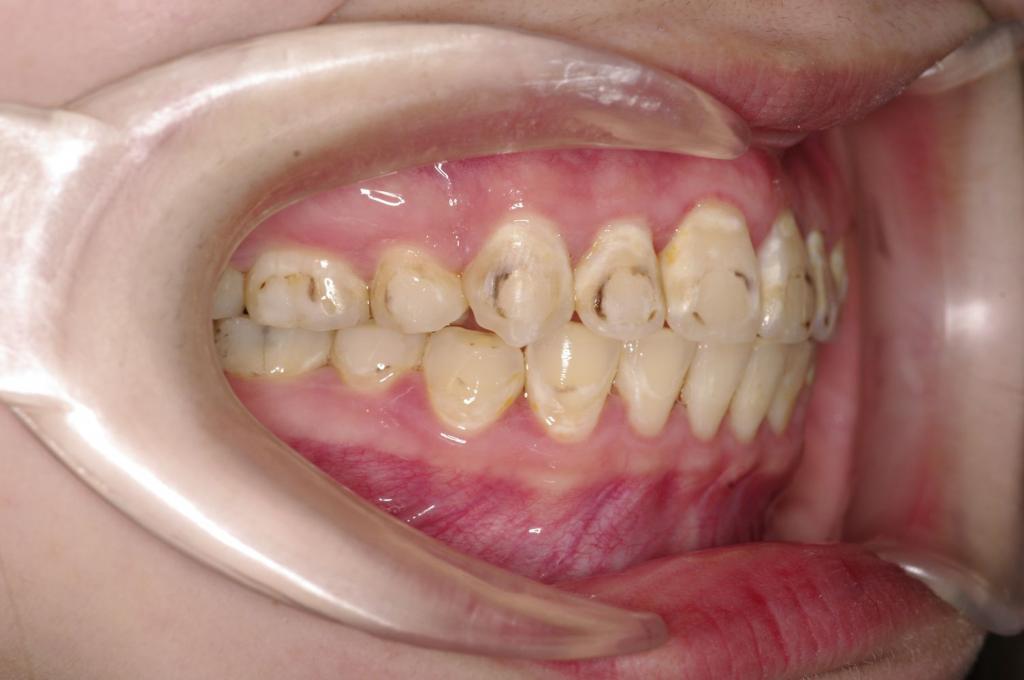

前歯、出っ歯・開咬の矯正治療

(治療期間、治療前後写真、治療方法、費用)WORKS